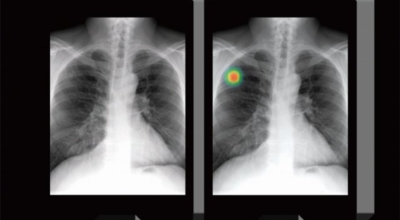

폐암 원인

폐암의 가장 큰 원인이며, 폐암 환자의 80-90%가 흡연에서 비롯될 수 있다고 할 수 있어요. 흡연을 자주 할 시 폐암 발생 위험이 흡연을 하지 않은 사람보다 13배가 증가를 할 수가 있고, 간접흡연 역시 1.5배나 폐암 걸릴 확률이 있어 흡연은 폐암 그 자체라고 생각하시면 될 것 같아요.